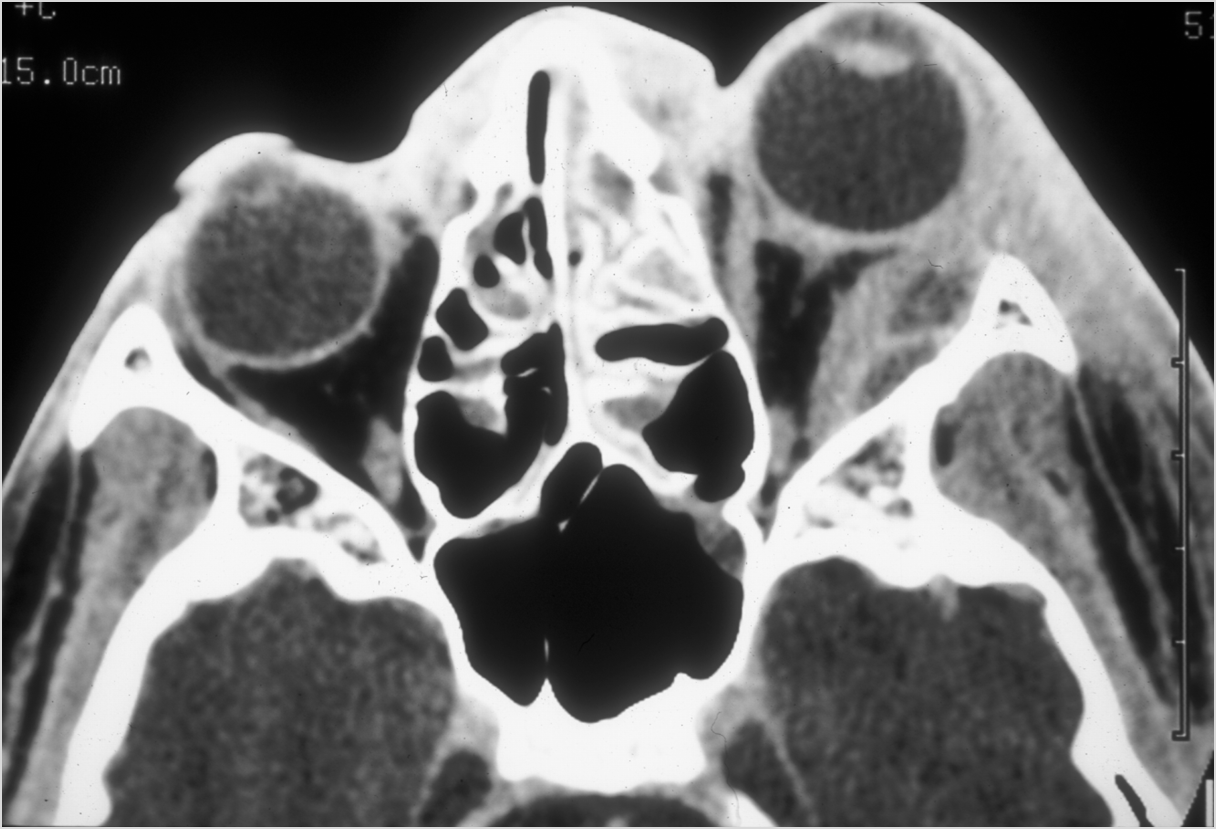

Nasal Cavity and Nasolacrimal Drainage System

There is mucoperiosteal thickening in the nasal cavity.

There is mucosal thickening of the posterior lateral walls of the nasal cavity, cribriform plate or the face of the sphenoid bone.

There is infiltration of soft tissues or bone erosion along the nasolacrimal fossa or canal.

Sinuses

There is soft tissue swelling anterior to the frontal sinus or in the soft tissues surrounding the maxillary sinuses.

There is mucoperiosteal thickening in the sinuses.

There is mucosal enhancement in the sinuses.

There is bone erosion along the walls of any affected sinuses.

There is an appearance of bone expansion, due to regressive remodeling and suggestive of pre-existing mucocele, along the walls of any affected sinuses.